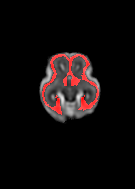

Fetal cortical plate segmentation is essential in quantitative analysis of fetal brain maturation and cortical folding. Manual segmentation of the cortical plate, or manual refinement of automatic segmentations is tedious and time-consuming. Automatic segmentation of the cortical plate, on the other hand, is challenged by the relatively low resolution of the reconstructed fetal brain MRI scans compared to the thin structure of the cortical plate, partial voluming, and the wide range of variations in the morphology of the cortical plate as the brain matures during gestation. To reduce the burden of manual refinement of segmentations, we have developed a new and powerful deep learning segmentation method. Our method exploits new deep attentive modules with mixed kernel convolutions within a fully convolutional neural network architecture that utilizes deep supervision and residual connections. We evaluated our method quantitatively based on several performance measures and expert evaluations. Results show that our method outperforms several state-of-the-art deep models for segmentation, as well as a state-of-the-art multi-atlas segmentation technique. We achieved average Dice similarity coefficient of 0.87, average Hausdorff distance of 0.96 mm, and average symmetric surface difference of 0.28 mm on reconstructed fetal brain MRI scans of fetuses scanned in the gestational age range of 16 to 39 weeks. With a computation time of less than 1 minute per fetal brain, our method can facilitate and accelerate large-scale studies on normal and altered fetal brain cortical maturation and folding.